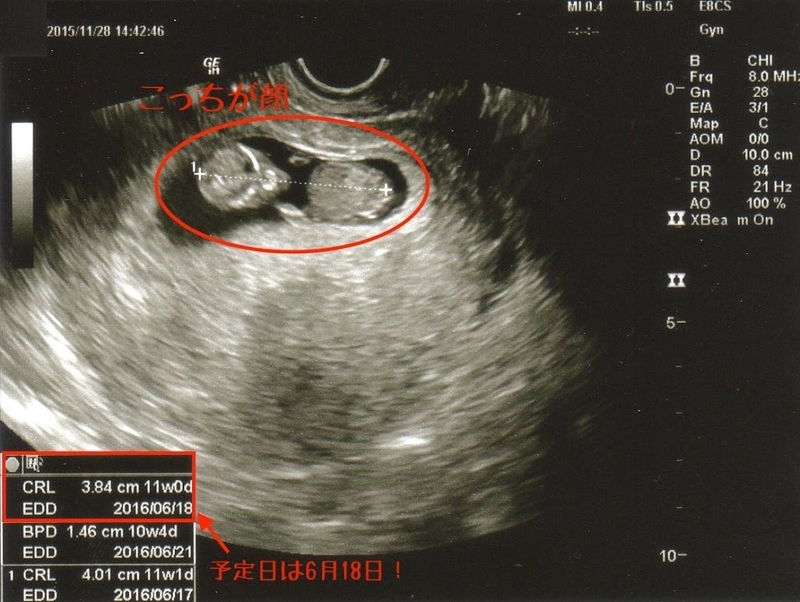

【準備】妻ご懐妊から11週間。

昨日は11週目で、予定日がわかるころだということで

病院に行ってきました。

着実に大きくなってます!

顔もわかるし、手足もちゃんとわかりました。

そしてもぞもぞと動いているところがちゃんと確認できました!

まだ3.8cmくらいなのですが、がんばって大きくなってます。

どうやら出産予定日は2016年6月18日になりそうです。